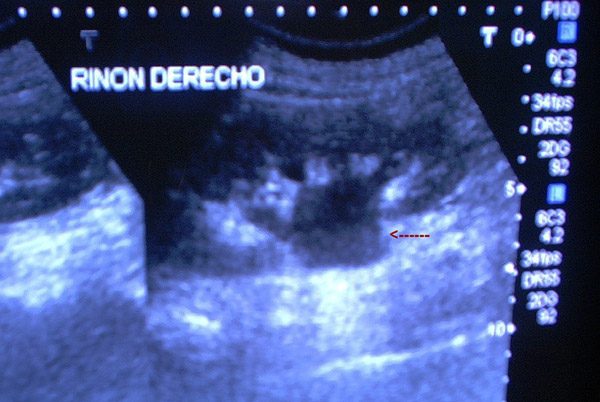

MO Ectasia pielocalicial.